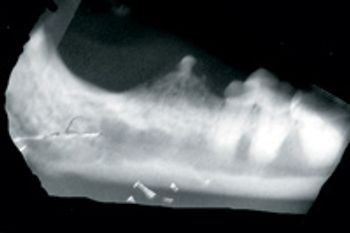

Q. How do you proceed when you have a cat anesthetized and find that a tooth (or teeth) you need to extract is fused to the mandible?